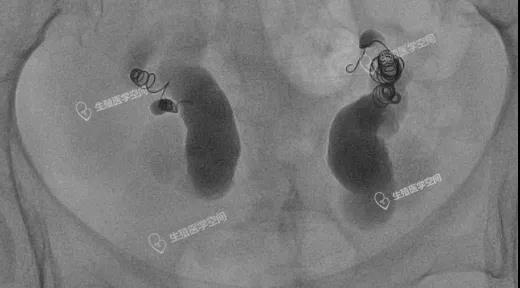

图5:双侧输卵管均栓塞多个弹簧圈

这两例都是所谓的致密栓塞,手术的医生自己也不自信,栓塞后手术结束前也不敢做一个造影看看效果。图4手术费花了1万9千多,右侧输卵管前几个弹簧圈掉进了宽大的积水管腔,没用一点栓塞作用。左侧输卵管栓塞是串联加并联。图5手术费是2万4千多,双侧输卵管栓塞的前几个弹簧圈都掉进了远段宽大的积水管腔,没用一点栓塞作用,起作用的就是最后一个弹簧圈。